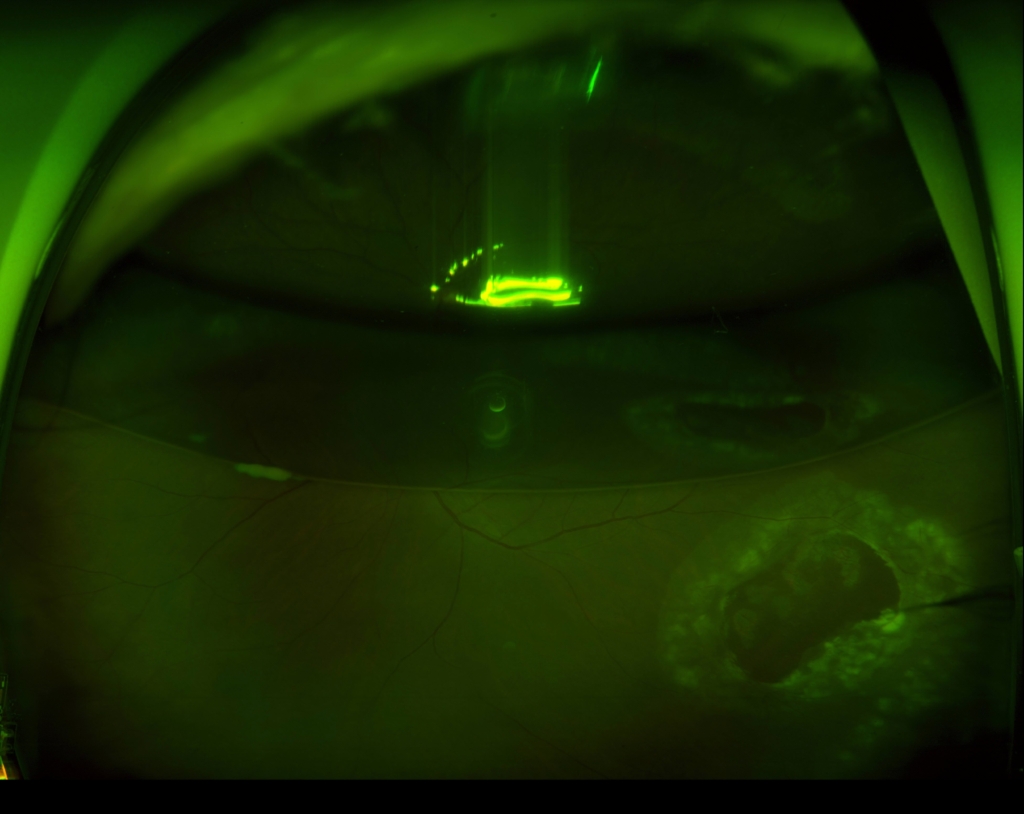

3時から8時に黄斑剥離を伴う胞状網膜剥離があり、4時に弁状裂孔がみられる。

12時から2時に格子状変性がみられる。